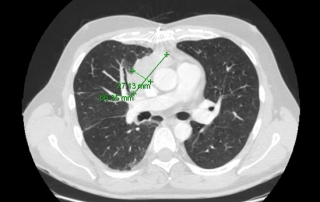

Scanner comparé au scanner avant traitement, la cible axillaire droite taille 18 x 9 mm

vs 32 x 31 mm soit une régression de 84% sur cette cible.